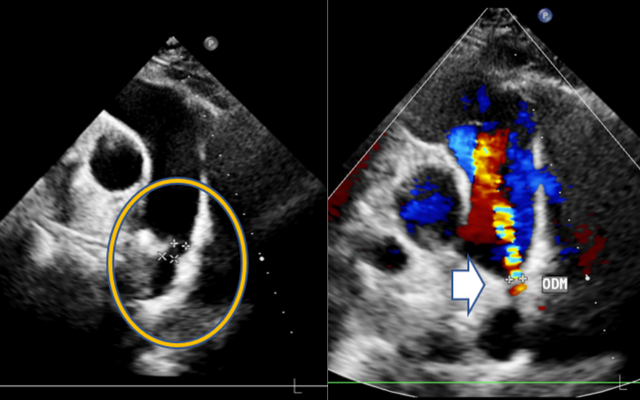

Ngay sau đó, chị N. được làm siêu âm tim. Kết quả cho thấy chị mắc còn ống động mạch - một dị tật tim bẩm sinh hiếm gặp ở người trưởng thành. Đây là tình trạng ống động mạch, vốn là mạch máu nối giữa động mạch chủ và động mạch phổi khi còn trong bào thai, không đóng lại sau khi trẻ chào đời. Ở trẻ sơ sinh, dị tật này thường được phát hiện và xử trí sớm, nhưng nếu tồn tại đến tuổi trưởng thành thì rất hiếm gặp, dễ gây ra nhiều biến chứng nguy hiểm như tăng áp phổi, suy tim...

Hình ảnh siêu âm ghi nhận còn ống động mạch

Chưa đầy một giờ đồng hồ, ê kíp đã thành công bít hoàn toàn ống động mạch cho bệnh nhân. Hình ảnh siêu âm sau can thiệp cho thấy không còn dòng chảy bất thường, dụng cụ cố định vững chắc. Chị N. nhanh chóng cải thiện triệu chứng, ổn định và xuất viện chỉ sau 2 ngày.